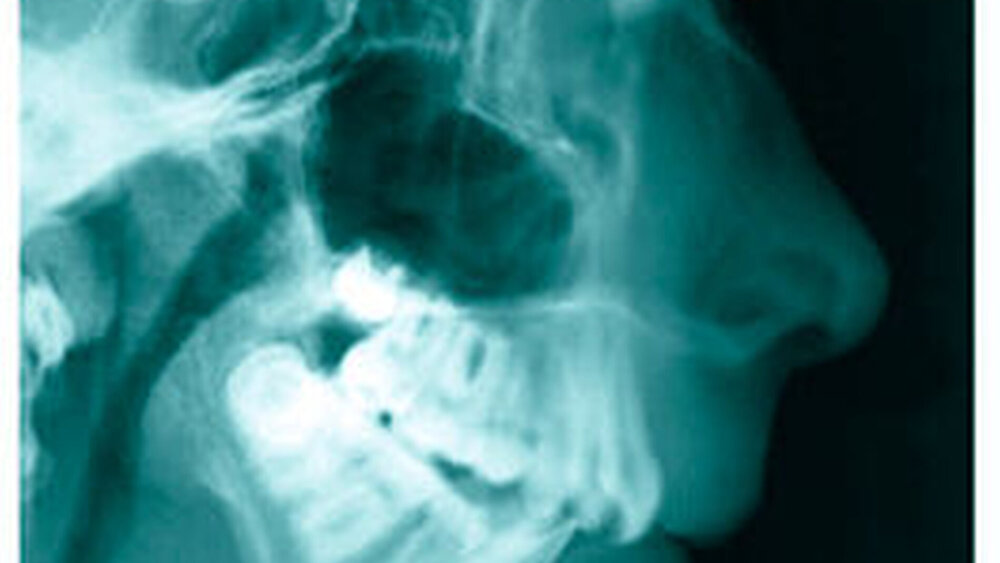

Bereits 2004 wies Carla Evans [Evans, 2005] auf das Risikomanagement bei Allgemeinerkrankungen hin und stellte am Beispiel der JIA dar, dass Unterkieferrücklagen und frontal offene Bisse aus der Kiefergelenkzerstörung entstehen können. Die Röntgenaufnahmen einer JIA-Patientin mit oligoartikulärer Form und Beteiligung des rechten Kiefergelenkes zeigen den typischen Verlauf sehr gut. Bei ursprünglich sehr dezenten Befunden, wie einer s-förmigen Mundöffnung von 44 mm, einer geringen Mittenabweichung um 2 mm nach rechts und einem frontal offenem Biss klagte sie über Schmerzen beim Essen, was den Anlass zur weiteren Diagnostik bot. Die erste Panoramaröntgenschichtaufnahme (Abbildung 1a-c) zeigt auf der rechten Seite einen abgeflachten Kondylus und eine bereits verstrichene Fossa condylaris. Ein Jahr später vermittelt das Fernröntgenseitenbild (Abbildung 1d) trotz fortschreitender kondylärer Resorption ein harmonisches Bild, während nach drei Jahren bei voranschreitendem Abbau des rechten Kondylus (Abbildung 1e) eine Rücklage der Mandibula und eine Bissöffnung manifest sind (Abbildung 1f).

Die Fernröntgenseitenaufnahme in Abbildung 2a zeigt ein „rheumatisches“ Profil mit retraler, hypoplastischer Mandibula, oft kombiniert mit einer Schwäche des M. masseter auf der betroffenen Seite. Der Funktionsschmerz erzeugt „Kaufaulheit“. Die Gesichtsasymmetrie (Abbildung 2b) betrifft meist Kinn, aufsteigenden Ast und die Höhe der Kieferwinkel. Auch die nicht dentoalveoläre Mittellinienverschiebung kann auf eine JIA hinweisen. Kreuzbisse variieren in Abhängigkeit vom Grad der Unterkiefermittenabweichung. Gemeinsame Auftreten eines frontal offenen Bisses und eines vergrößerten Overjet sind als klinische Anzeichen zu bewerten.